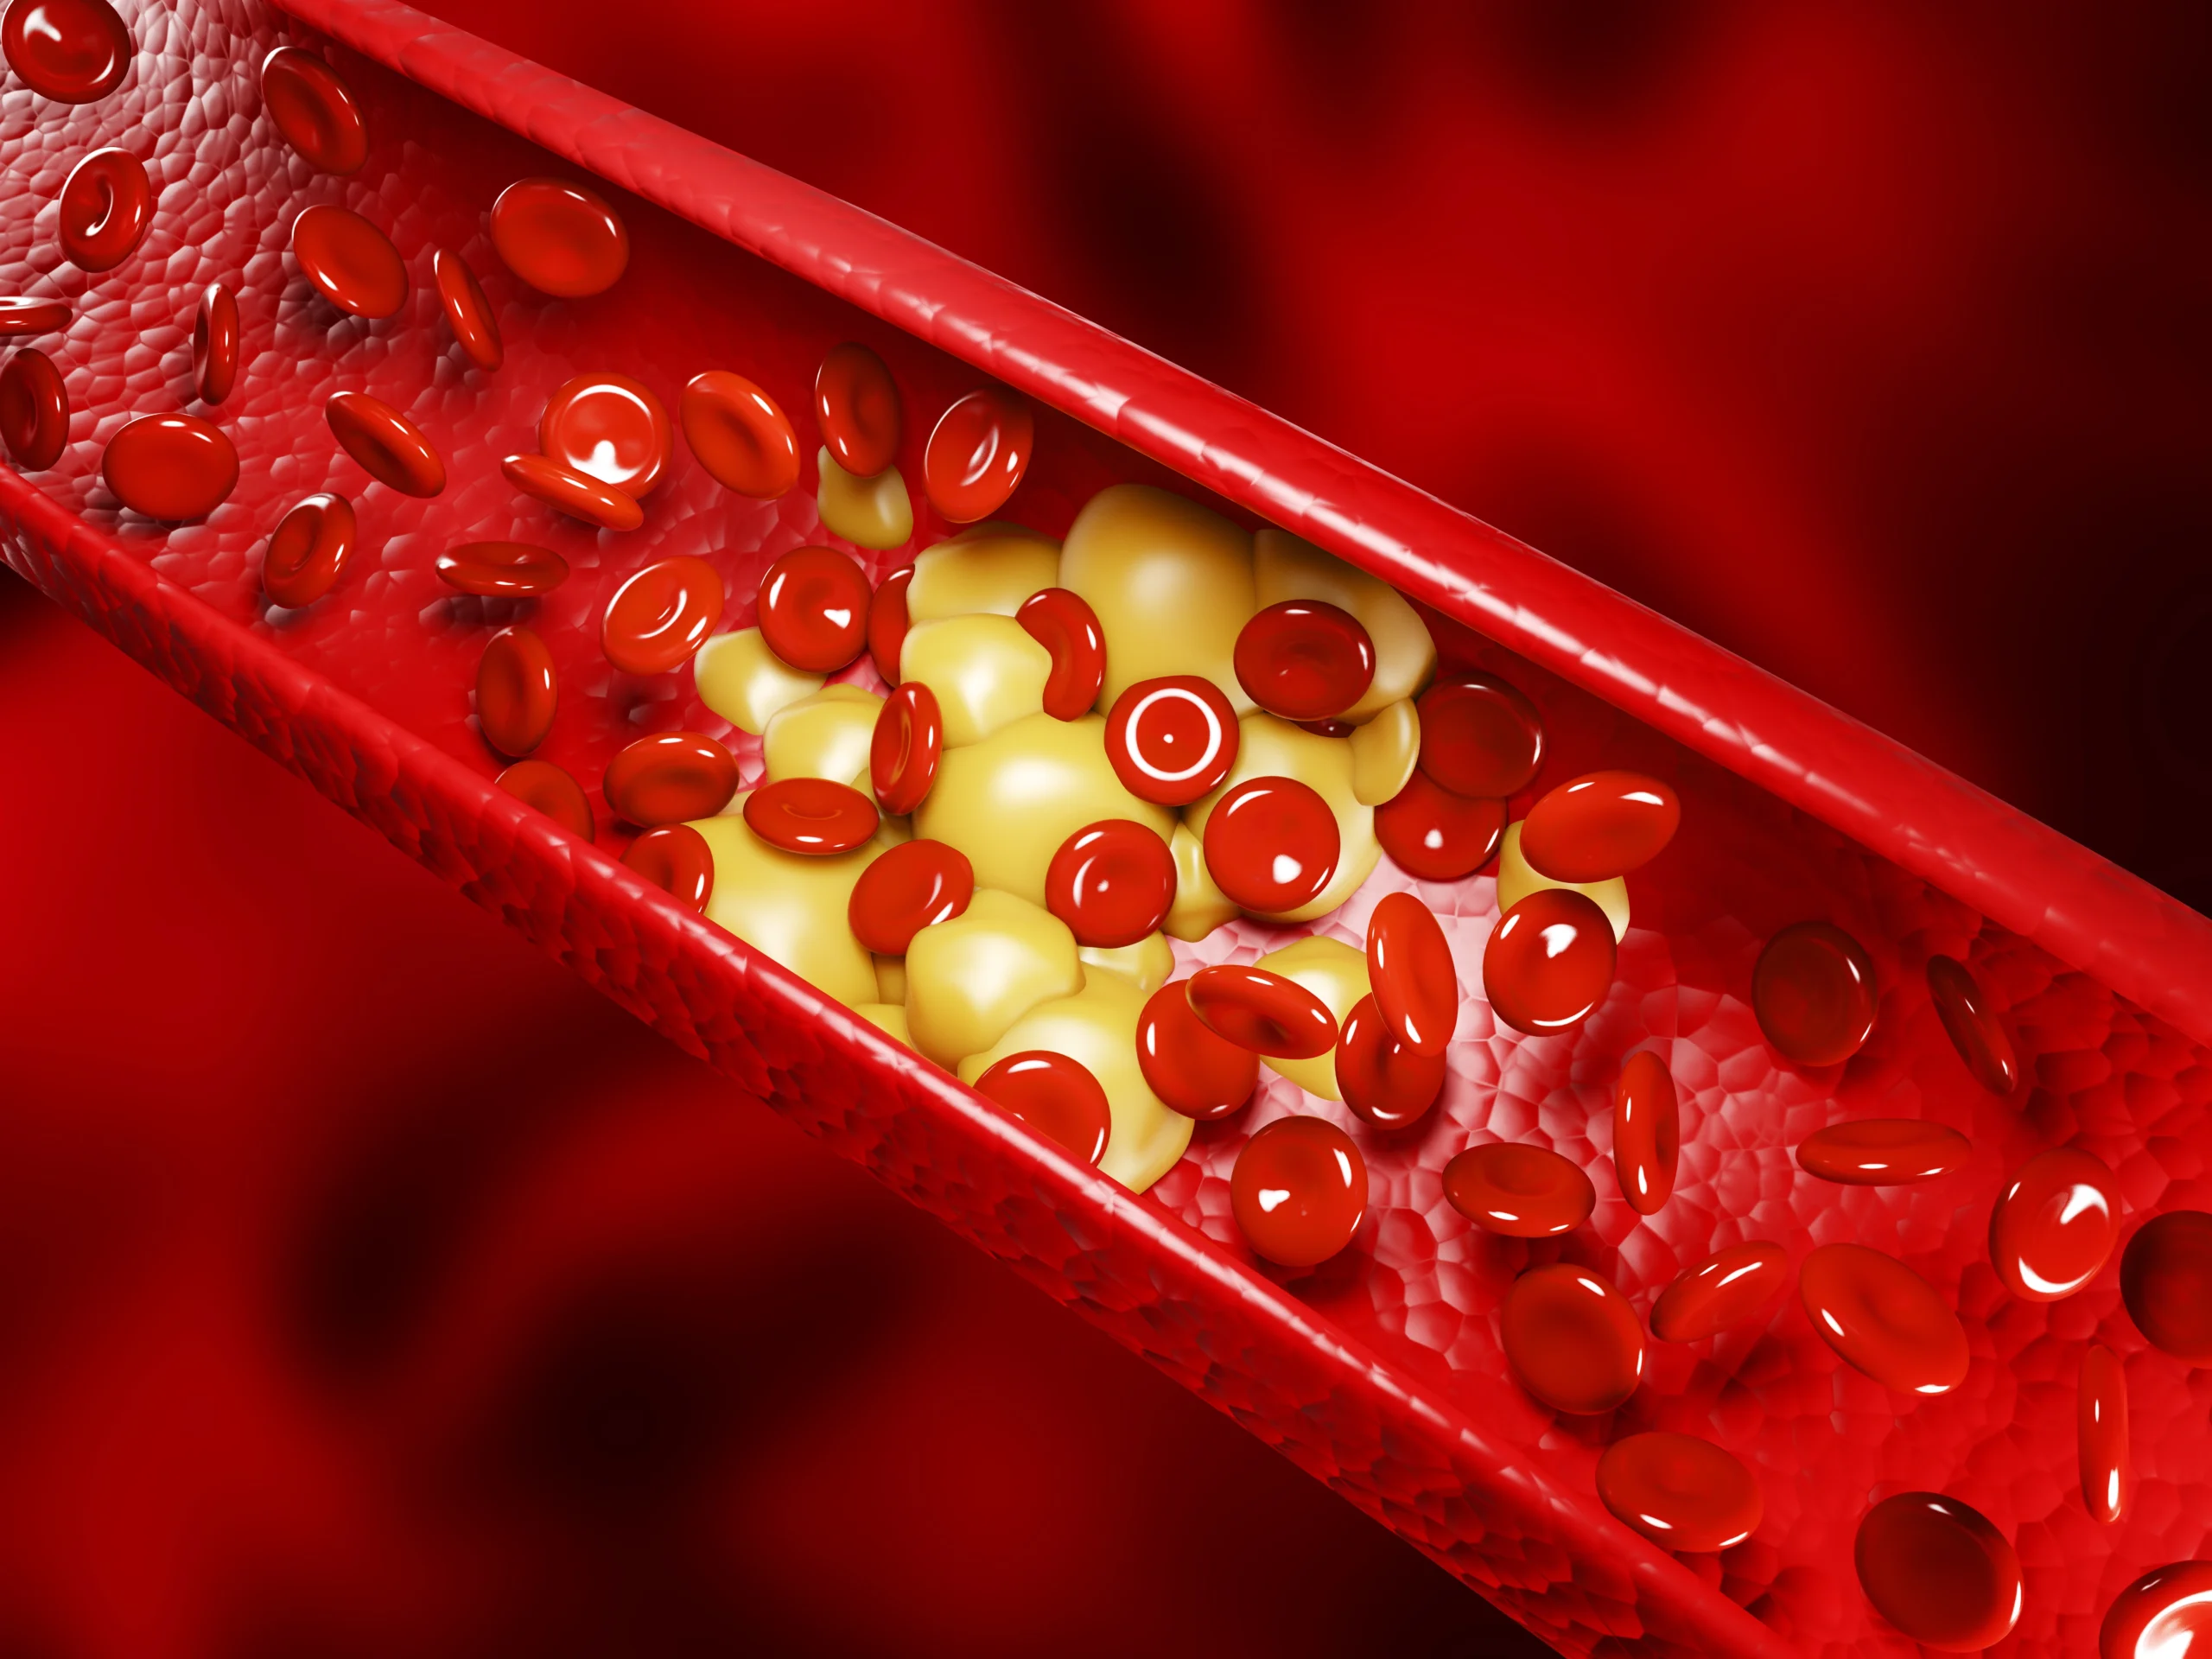

Penyakit ini terjadi karena adanya penumpukan kristal urat pada persendian. Kondisi inilah yang mengakibatkan peradangan, pembengkakan, hingga rasa nyeri hebat dari serangan asam urat.

Hasil dari proses pengolahan purin endogen dan eksogen yaitu asam urat. Asam urat sebenarnya bisa larut dalam darah, namun terkadang tubuh memproduksi terlalu banyak asam urat atau ginjal yang terlalu sedikit mengeluarkan asam urat. Kondisi ini bisa menyebabkan penumpukan asam urat dan membentuk kristal urat yang tajam sehingga menimbulkan rasa nyeri, pembengkakan dan peradangan.

Jika tidak segera tertangani, maka kristal dapat membentuk gumpalan di bawah kulit pada persendian yang disebut dengan tophi. Kristal yang menumpuk di saluran kemih juga dapat membentuk batu gin.

Ya, kadar asam urat yang tinggi dapat menyebabkan radang sendi. Ketika kristal asam urat menumpuk di persendian, kondisi ini memicu peradangan, pembengkakan, dan rasa nyeri hebat yang dikenal sebagai arthritis gout.